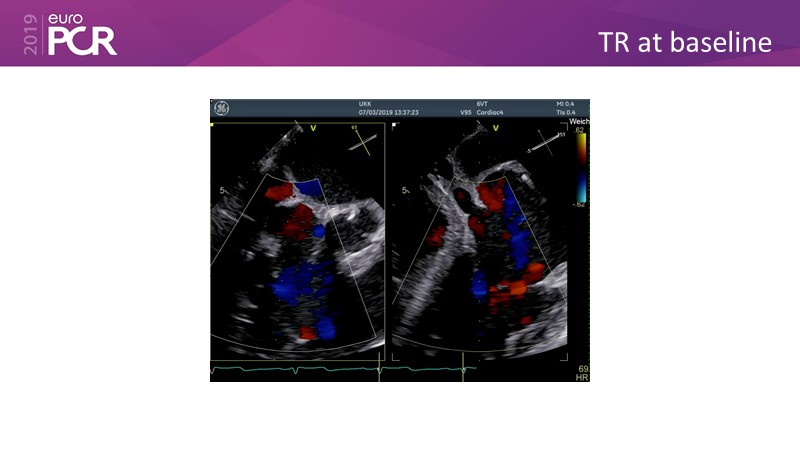

Addressing tricuspid regurgitation with annular reduction: the Cardioband tricuspid system

Consult this session to understand how patients with tricuspid regurgitation and annular dilatation can benefit from Cardioband system...

- To understand how patients with tricuspid regurgitation and annular dilatation can benefit from Cardioband system